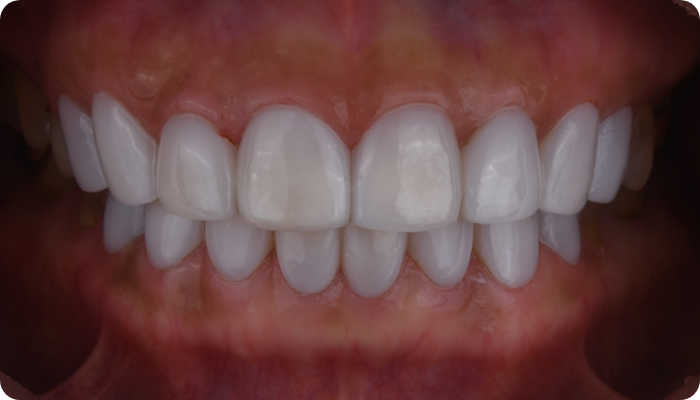

더서울치과의원은 정확한 안모 분석을 통한 프로파일 예측 치료로 심미성은 물론 치아 본연의 기능 회복까지 가능하도록

안면 근육과 기능, 치아 형태, 비율, 크기, 교합, 색감 등 전반적인 비율을 맞추어 본인에게 잘 맞는 치아의 형태로 복원합니다.

단순하게 예쁘고, 심미적으로 만드는 인위적인 작업물이 아닌,

자연치아와 가장 유사하도록 치아를 복구하는데에 초점을 맞추어

치아복구 + 치아성형 2가지의 장점을 합쳐

개개인 손상 정도에 따른 맞춤형 보철을 제작합니다.